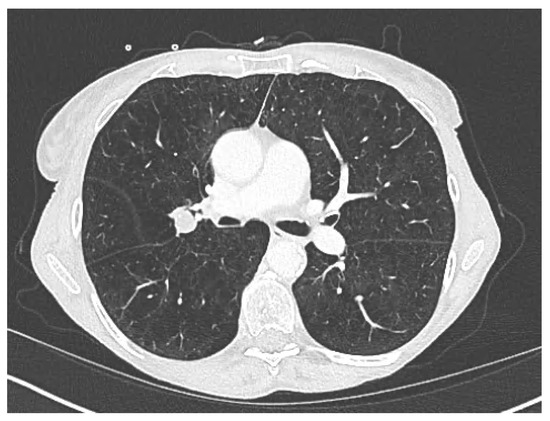

Lung Stereotactic Body Radiation Therapy in a Patient with Severe Lung Function Impairment Allowed by Gallium-68 Perfusion PET/CT Imaging: A Case Report

Lucia, F.; Hamya, M.; Pinot, F.; Bourhis, D.; Le Roux, P.-Y. Lung Stereotactic Body Radiation Therapy in a Patient with Severe Lung Function Impairment Allowed by Gallium-68 Perfusion PET/CT Imaging: A Case Report. Diagnostics 2023, 13, 718. https://doi.org/10.3390/diagnostics13040718